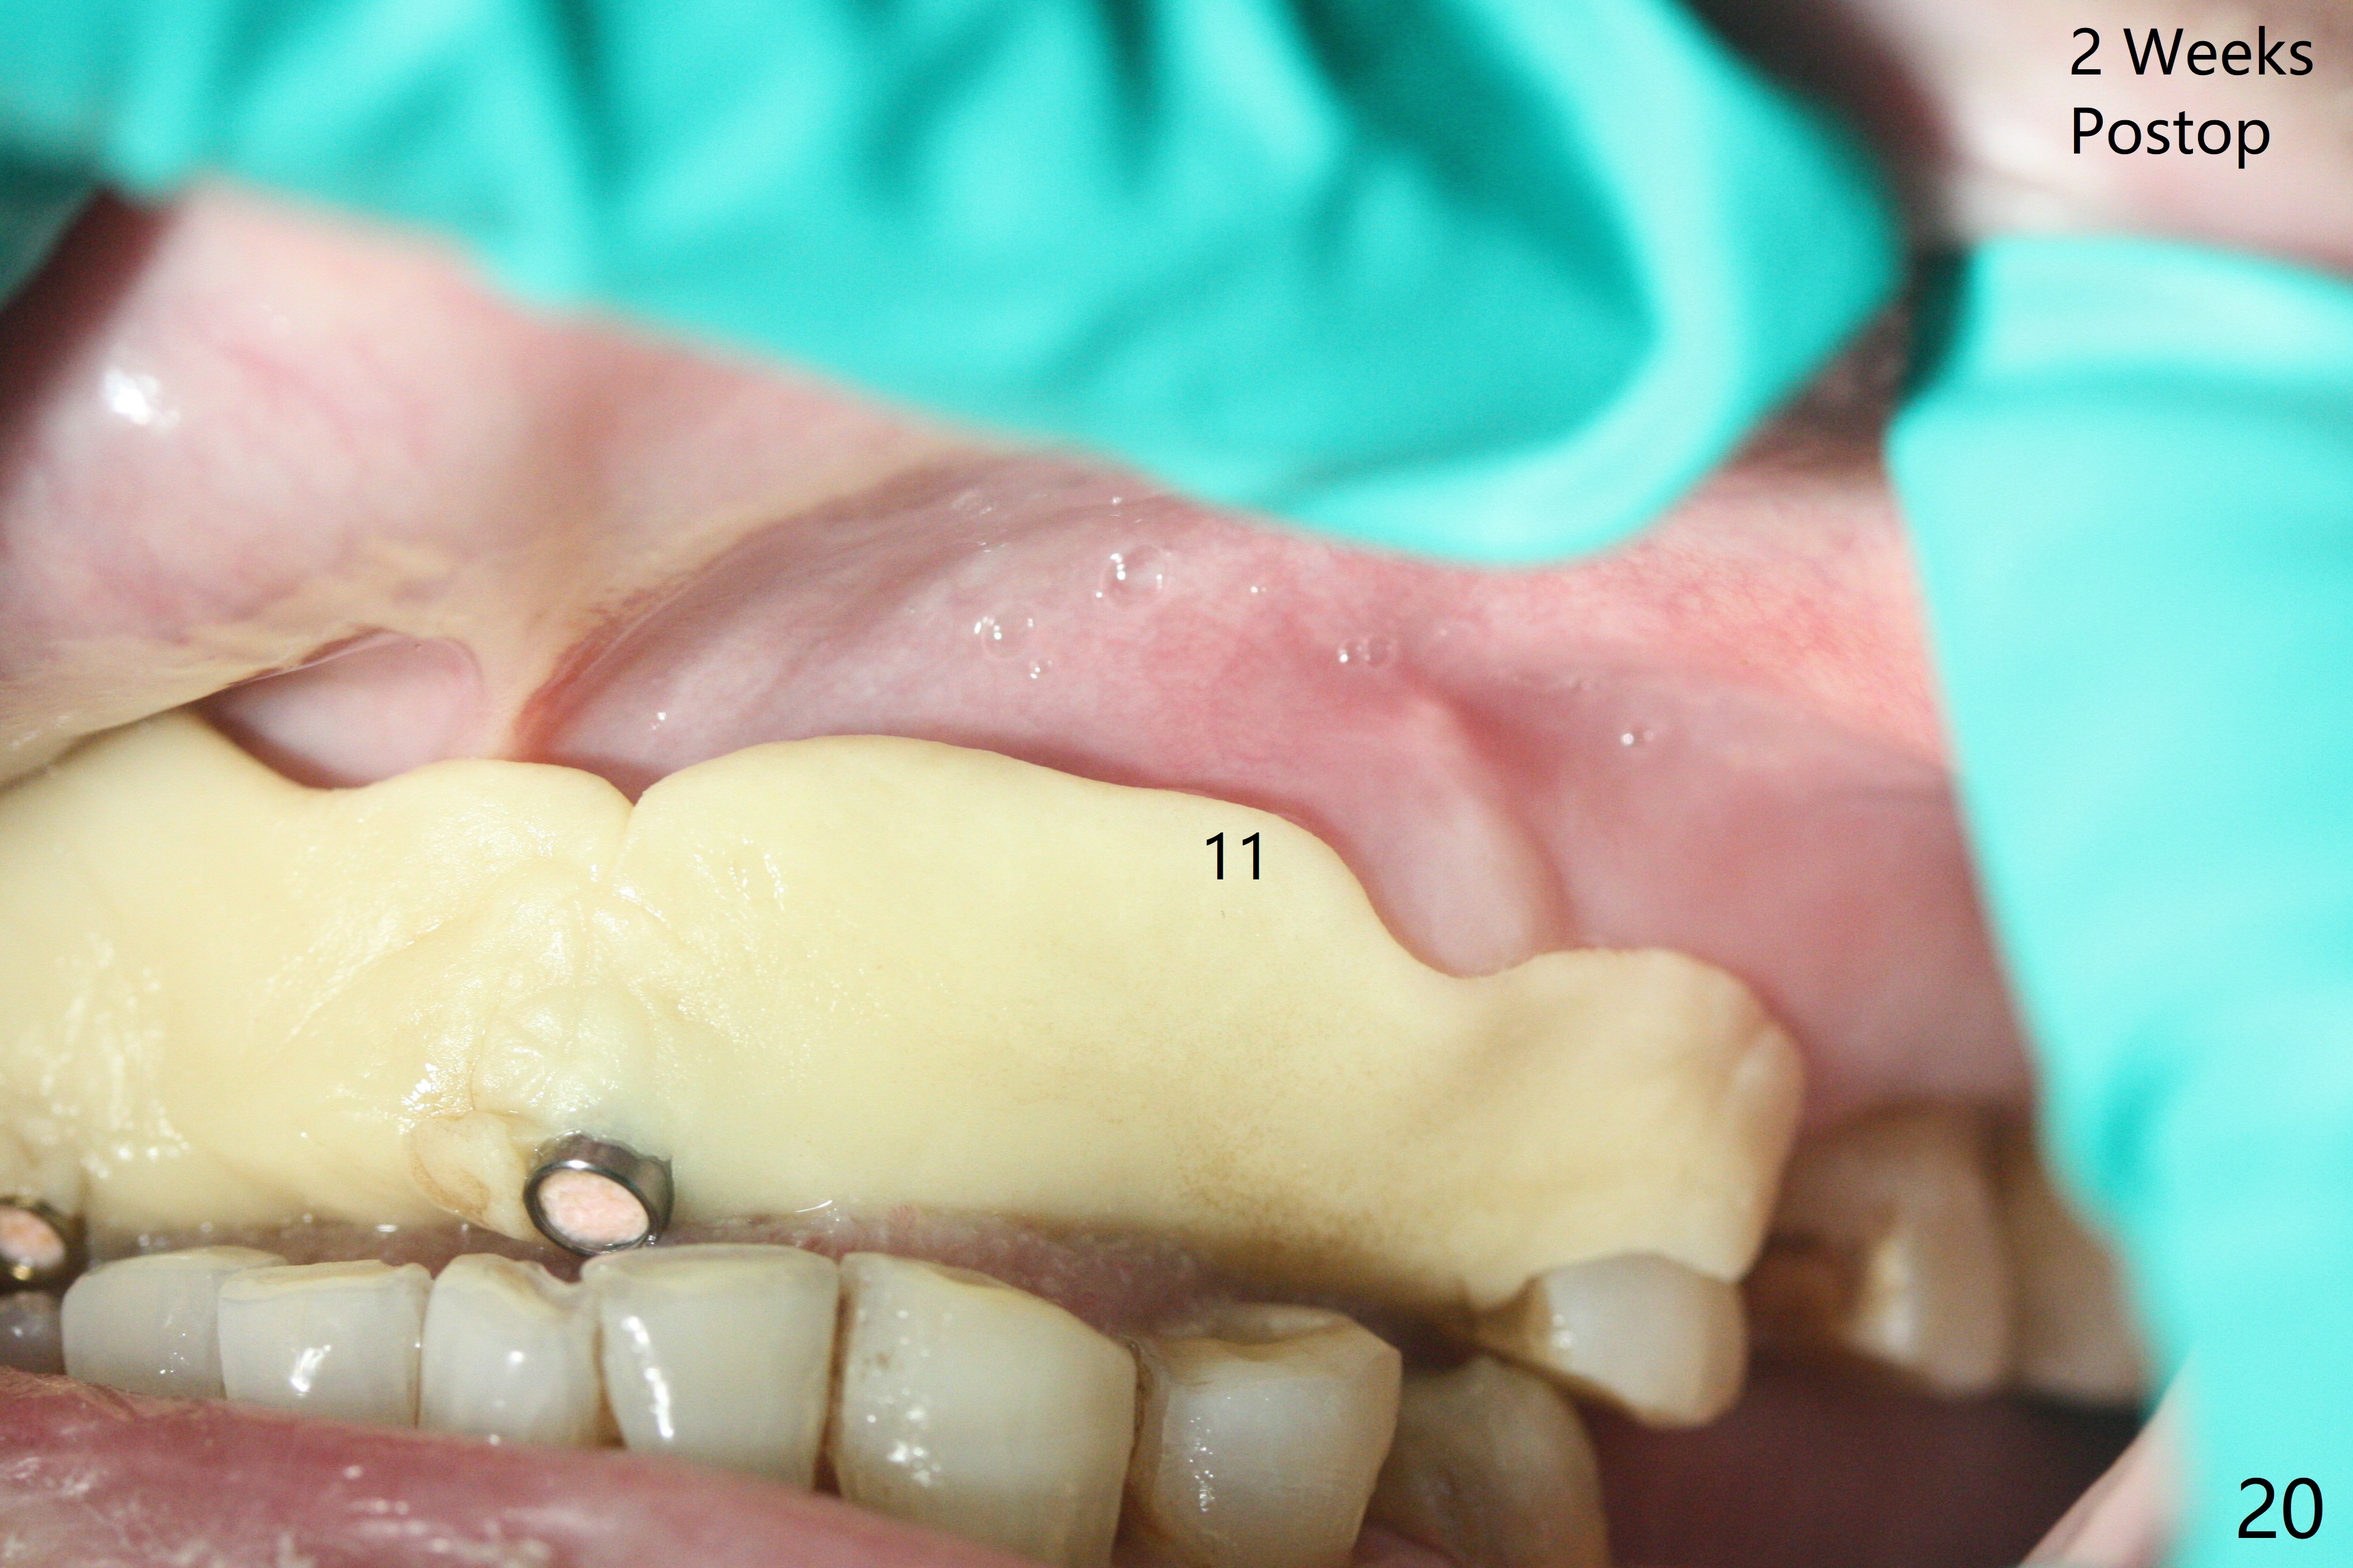

今天下午进入治疗室,粘性骨粉已制备:上清液来自红管(含促凝剂),离心3分钟(图一);再离心10分钟上清液就转变PRF,压制后,使用前剪成三块(图二:黑线),其中两块punch一个洞(图二:圆圈),插入7,9号牙基台固定;大块覆盖11/12号牙牙槽窝(图十四)。7,9,11,12号牙必须拔除(图三),然后在7,9,12种植。由于缺失左下磨牙,前牙垂直距离减少(图四)。完成9号牙位钻洞后,利用fixture mount(图五:M)植入植体,并留在原位固定导板(图六),然后7号牙种植,也留下fixture mount(图六:7,9),最后完成12号牙植入,但是后者扭力低,放置愈合螺帽(图九),而7,9号牙位放置修复基台(图七,八(使用5.5毫米profile drill后),好像基台没有完全就位。7号牙位更换基台似乎没帮助(图十),9号牙位再次放置同一个基台临床上仿佛有改变(比较图八与十二)。放置粘性骨粉后(图十一至十三),牙槽窝口覆盖PRF膜(图十四:P(A:基台)),最后使用树脂敷料固定骨粉和膜(图十五,六),基台帮助敷料固位,没有咬合干扰(图十七:*)。树脂敷料部分解决美观问题,一个月后撤除,如果植体仍有稳定性,可能制作7-10临时牙桥,可能部分维持或者恢复牙龈外形。术后一周病人主诉后面植牙和鼻底疼痛,11号牙根尖牙龈充血(图十八),轻度触痛,可能与术中尚未完全清创有关(图十九(术前CT 3D图像))。再服用Amoxicillin一周,症状好转,鼻底轻度触痛(图二十)。术后1.5月没有任何不适,撤除树脂敷料,7号牙基台(袖)显得太长,换一个短的(4.5x4(5)(图十,十一)->4x4(3)毫米)毫米),植骨好像愈合正常(图二十一:*)。7号牙换了短的基台,9号牙基台高度调整后,与对合牙有足够空间做临时牙桥,最好8,10号牙位牙龈应该凹陷(图二十二:*),有pontic外形。另外9号牙基台颊侧牙龈边缘有所修整,临时牙桥准备。先做7-10临时牙桥,理想临时牙桥pontic处树脂应该多些(图二十三:白线)压迫牙龈形成凹陷。11,12号牙牙槽窝在树脂(Bosworth)敷料下也正常愈合(图二十四)。